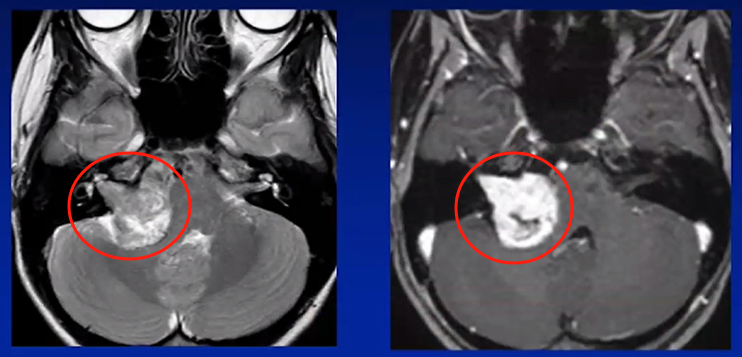

娜娜的听神经瘤巨大,典型的“冰淇淋”征象,“冰淇淋尾”是听瘤粘附着骨质内听道里面听神经的所在之处,也是肿瘤难以全切、易导致面瘫和听力下降的关键。

术前MRI

“怀疑是听神经瘤,看到影像片子上这个像冰淇淋一样的异常阴影了吗?这是听神经瘤典型的‘冰淇淋’征影像表现”,看着医生指着影像片子上自己右侧脑子影像的“冰淇淋”,娜娜陷入恐惧。

术后7年MRI